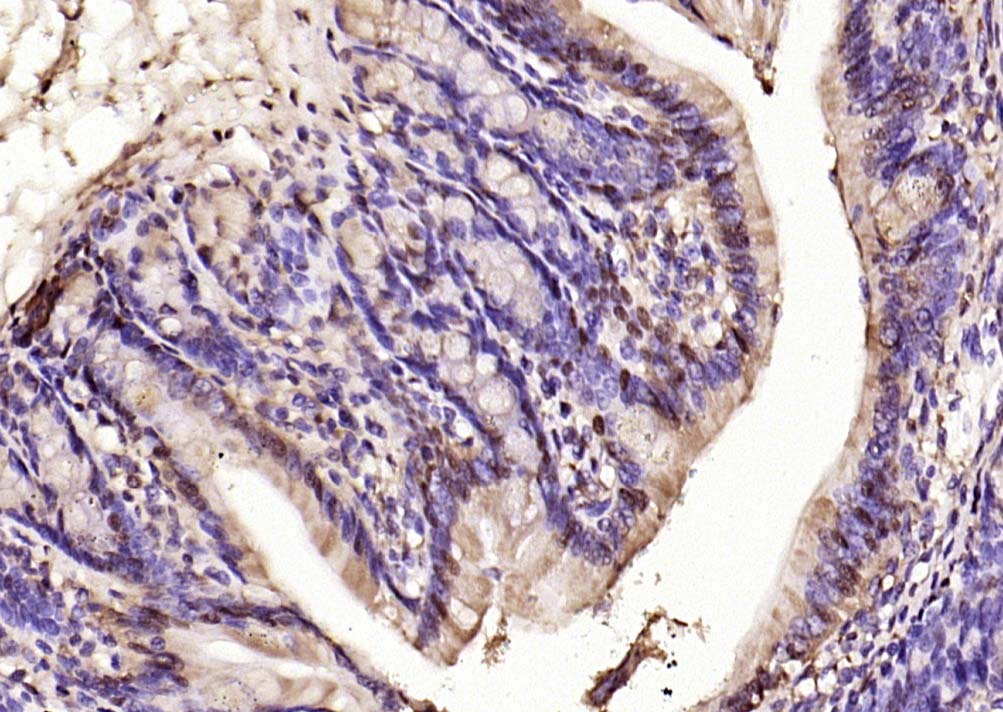

phospho-ERK1/2 (Thr202 + Tyr204) Rabbit pAb

| IHC-P, IHC-F, IF |

| Dilution | IHC-P=1:100-500,IHC-F=1:100-500,ICC/IF=1:100-500,IF=1:100-500,Flow-Cyt=1 µg /test |